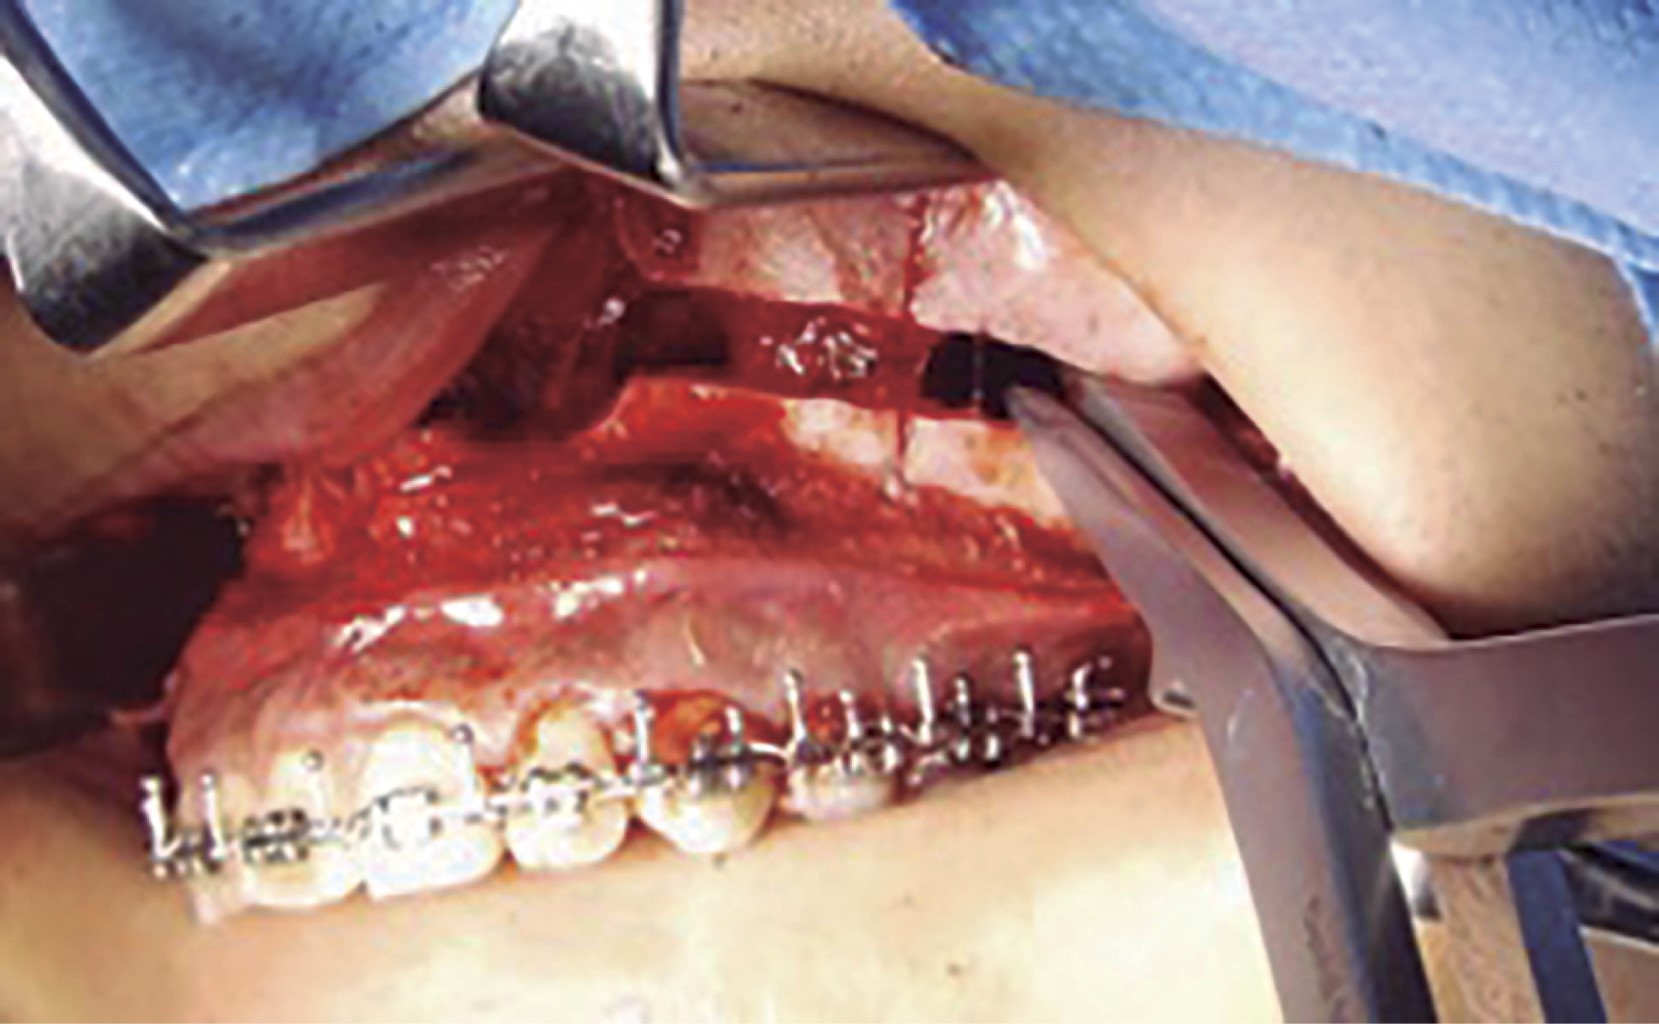

Se procede a la disección de la mucosa nasal. En el piso de la fosa nasal ha de disecarse hasta 30 mm a posterior (Figura 2) y enseguida se efectúa marcaje sobre el lecho óseo de acuerdo al tipo de osteotomía a realizar. Se colocan marcas de referencia (Figura 3). Se realiza osteotomía con sierra reciprocante, iniciando en la pared lateral de la apertura piriforme, protegiendo la mucosa nasal previamente con una legra, hasta la región pterigomaxilar. Una vez completado el corte se realiza la disyunción de las apófisis pterigoides laterales y mediales del seno maxilar mediante osteótomos y se procede a realizar el descenso maxilar introduciendo pinzas de Smith en la osteotomía del buttress maxilomalar (Figura 4), de manera gradual y verificando la integridad de la mucosa nasal. Se realiza este paso de manera bilateral. Se procede a introducir cincel de septum en la apertura piriforme (Figura 5). Se inserta la pinza de Smith en el buttress anterior y de igual forma se abre de manera gradual verificando también la integridad de tejidos blandos. Se completa la disyunción del maxilar y se moviliza en su totalidad: anterior, lateral e inferiormente (Figura 6). Se regularizan espículas, si las hay, y se reposiciona el maxilar de acuerdo a lo planeado para la cirugía. Se fija el maxilar con miniplacas de osteosíntesis en L en la región medial del buttress nasomaxilar y en el buttress cigomaticomaxilar ambos de manera bilateral, se verifica hemostasia y se colocan puntos de sutura en la mucosa maxilar. Se procede a seguir con la cirugía ortognática.2,6,14,15,19

Figura 5